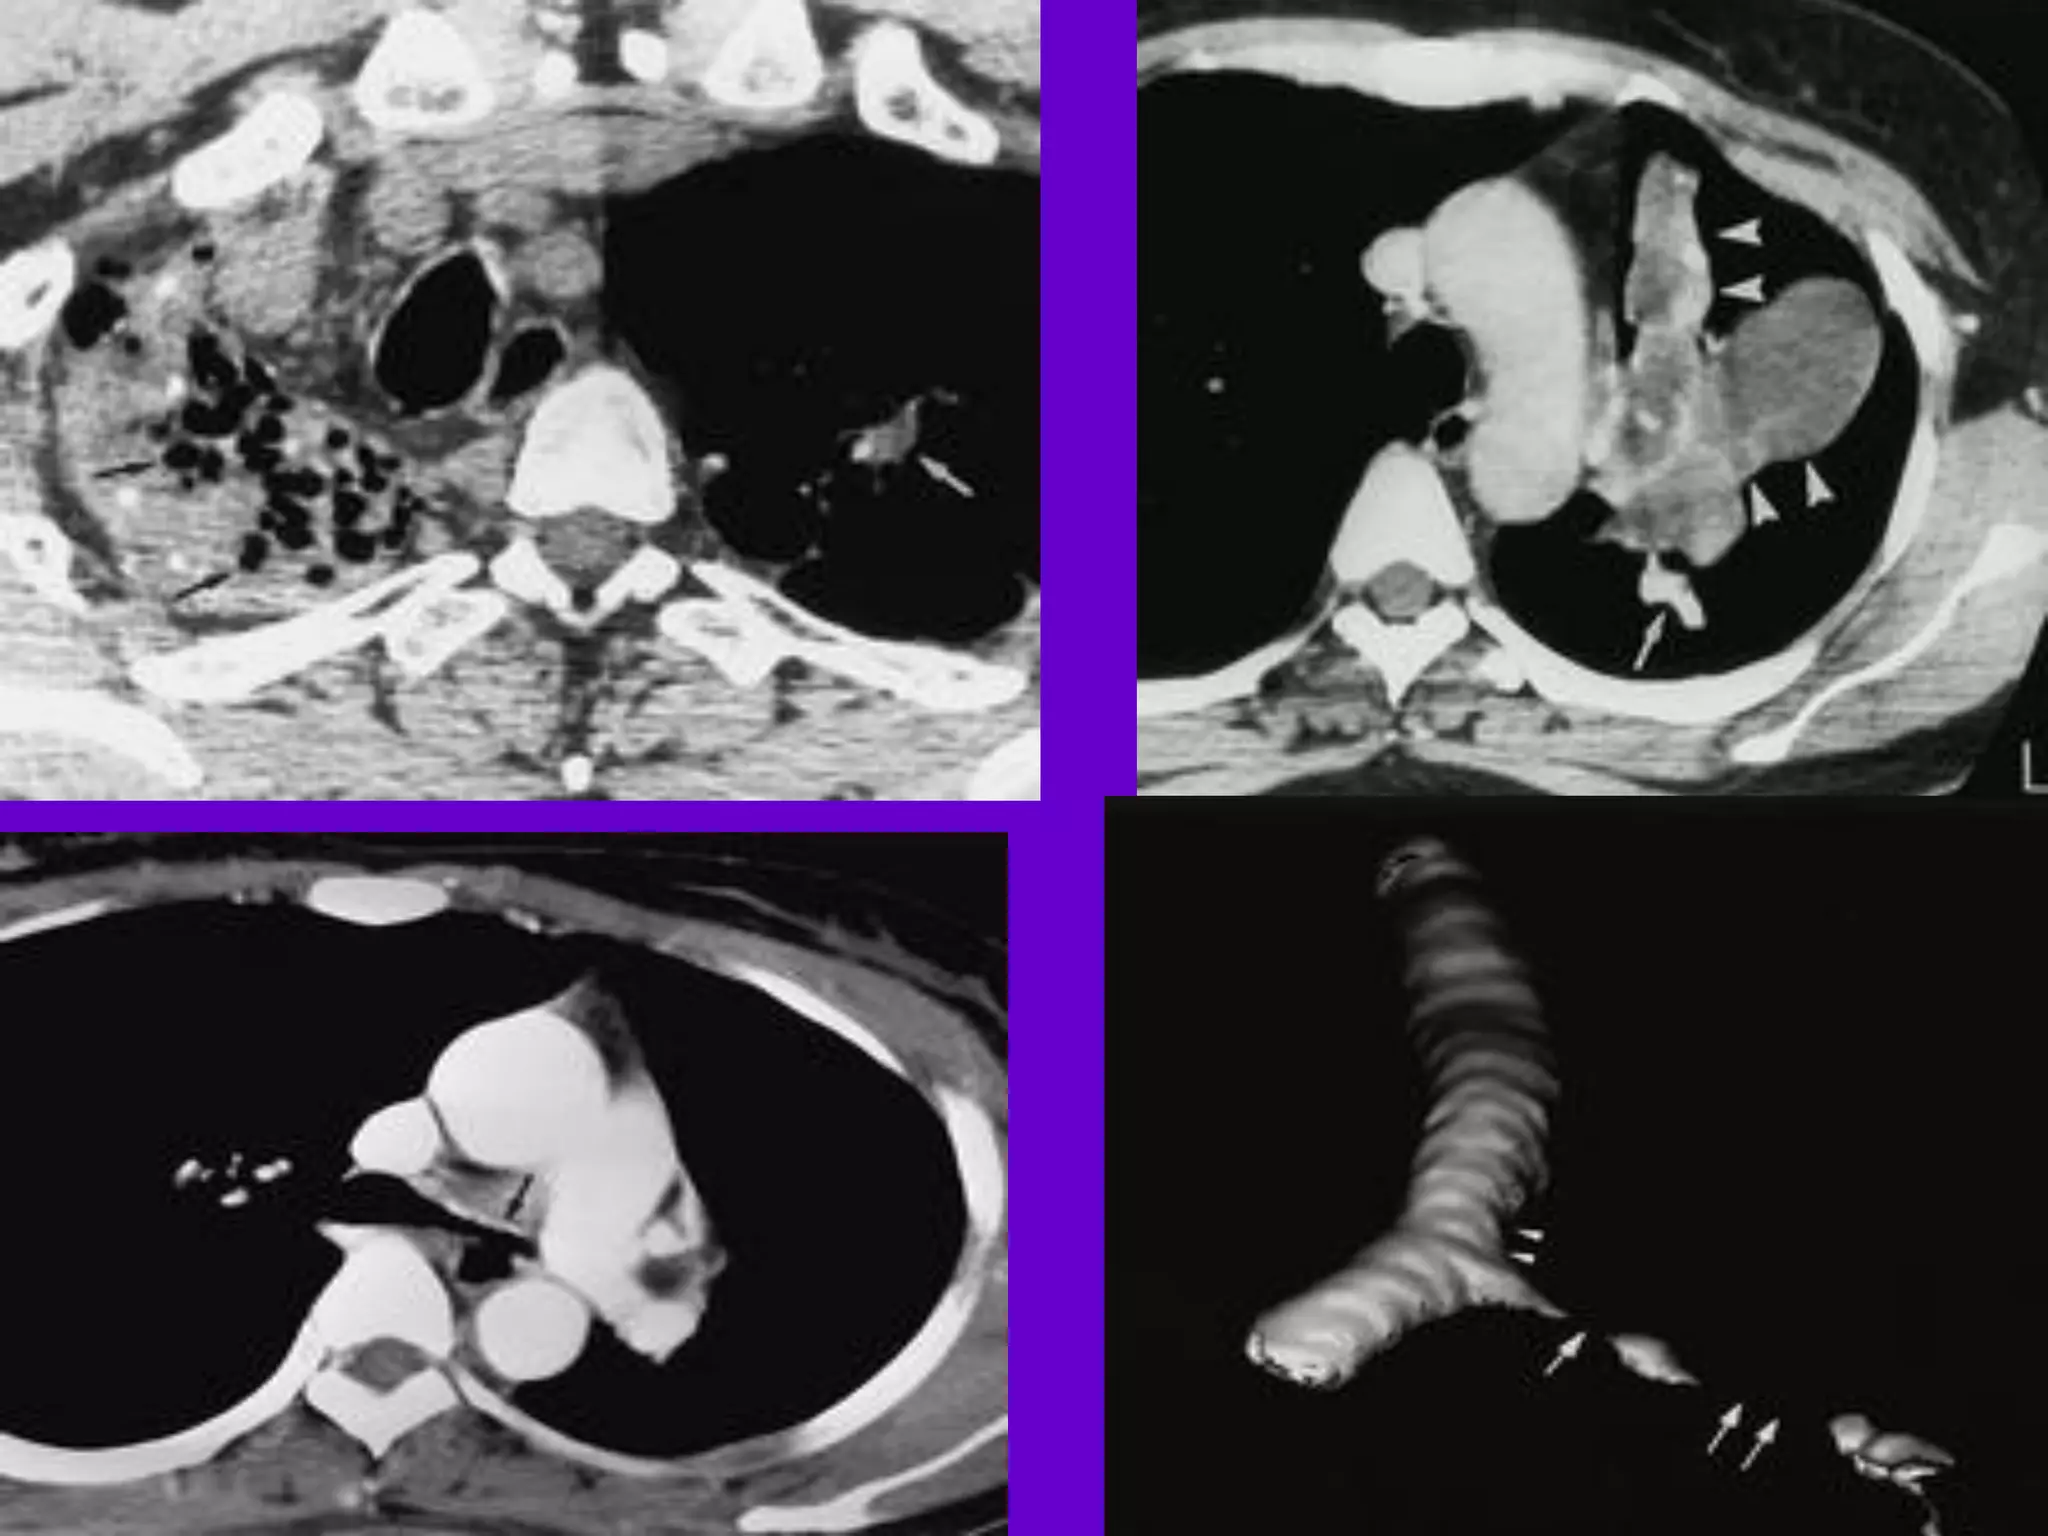

• 93.

CT Scan andMRI Scan in the diagnosis of TB 􀂄 The advent of CT and MRI imaging in the last two decades has redefined the approach in analysis of various diseases including TB.* 􀂄 CT and MRI have shown several advantages over conventional radiology in early diagnosis and follow-up of TB in different parts of the body. *Buxi TBS Indian J Pediatr 2002;69:965-972

• 94.

Pulmonary TB : LobarPneumonia 􀂄 CT is superior than plain CXR in picking up the consolidation, atelectasis and the hilar LN thereby making the diagnosis easy. 􀂄 MRI reveals some of these changes, however, CT is the diagnostic modality of choice in such cases. 􀂄 Bronchopneumonia 􀂄 On CT it is usually B/L and widespread, not always symmetrical involvement of lungs. 􀂄

• 95.

Hilar and Mediastinal Lymphadenopathy CTand MRI depict the hilar and mediastinal LN equally well. 􀂄 Calcification in the nodes is however better seen on CT. 􀂄 Necrosis is seen as focal areas of low attenuation on a CECT. 􀂄 On MRI focal necrosis is seen as areas of increased signal intensity on T2W images. 􀂄 EBTB 􀂄 HRCT is sensitive in the detection of early endobronchial spread of disease. 􀂄

• 98.

Skeletal TB Pott’s Disease(vertebral TB) 􀂄 CT and MRI helps in demonstrating a small focus of vertebral body involvement and defining the extent of the disease. 􀂄 CT/MRI help to evaluate TB involving the craniovertebral junction, sacro-iliac joint and posterior appendages. 􀂄 They are also helpful in assessment of spinal canal encroachment , posterior element involvement and in deciding the surgical approach. 􀂄

• 99.

GIT TB Strictures ofthe small bowel, mucosal edema and thickening are well visualized on CT. 􀂄 MRI depicts the para-aortic, aortocaval and mesentric lymph nodes effectively. 􀂄 GUT TB 􀂄 Various patterns of hydronephrosis may be seen at MR urography. 􀂄 MRI helps to differentiate macronodular TB lesions from the other mass lesions. 􀂄